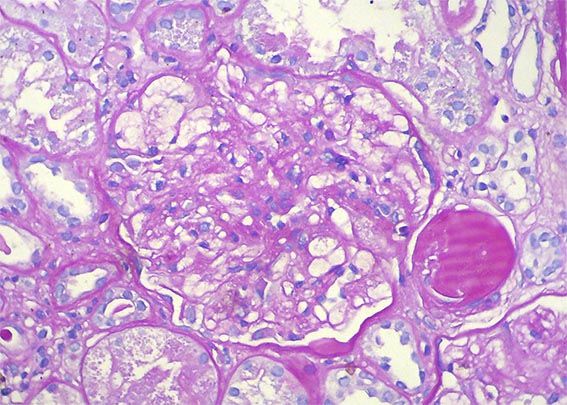

The patient is a 49-year-old man who was kidney transplanted nine years ago. Normal graft function, without proteinuria, until the 8th year, when he started to present mild proteinuria that gradually increased to 2.8 g/24 hours. Serum creatinine has also increased to 1.6 mg/dL.

Other tests: Hb: 9.5 mg/dL, Hto: 30.2 % (he has had multiple transfusions for anemia, since before transplantation), severe dyslipidemia: Triglycerides: 488, total cholesterol 480 mg/dL, VLDL: 209 mg/dL, LDL: 2 mg/dL, HDL: 3 mg/dL. Tests for autoimmunity, complement and viruses: Negative or normal. Ultrasound of the graft: Normal. On examination: Corneas opaque bluish with peripheral white halo, without visual impairment. No other alterations.

See the images of the biopsy.

Figure 4. PAS, X400.